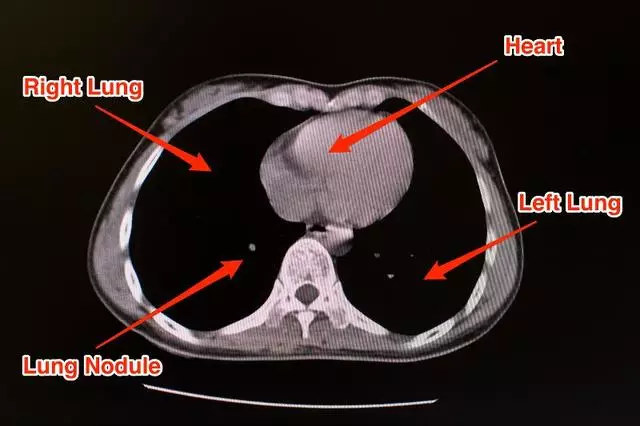

This is what a CT scan of a healthy patient looks like.

Now let's consider the CT scan of a patient who's suffering from pneumonia brought on by COVID-19.

Generally, pneumonia causes fluid to build up in the lung, which manifests itself as opacities in the lung. The literature on application of deep learning to diagnose COVID-19 using CT scans does point to some distinct characteristic features found in lung CT scans of COVID-19 as compared to other types of pneumonia, resulting from different causes.

A paper, titled Deep Learning System to Screen Coronavirus Disease 2019 Pneumonia, lists three such characteristics:

"...ground-glass appearance, striking peripheral distribution along with the pleura, and usually more than one independent focus of infections for one case."

- The first means that the opacities in the lung look like ground-glass.

- The second means that the majority of these opacities occur along the edge of the lung.

- The third means that we can have more than one such cluster of opacities.

All three of these characteristics can be observed in the CT scan image of the lung above.